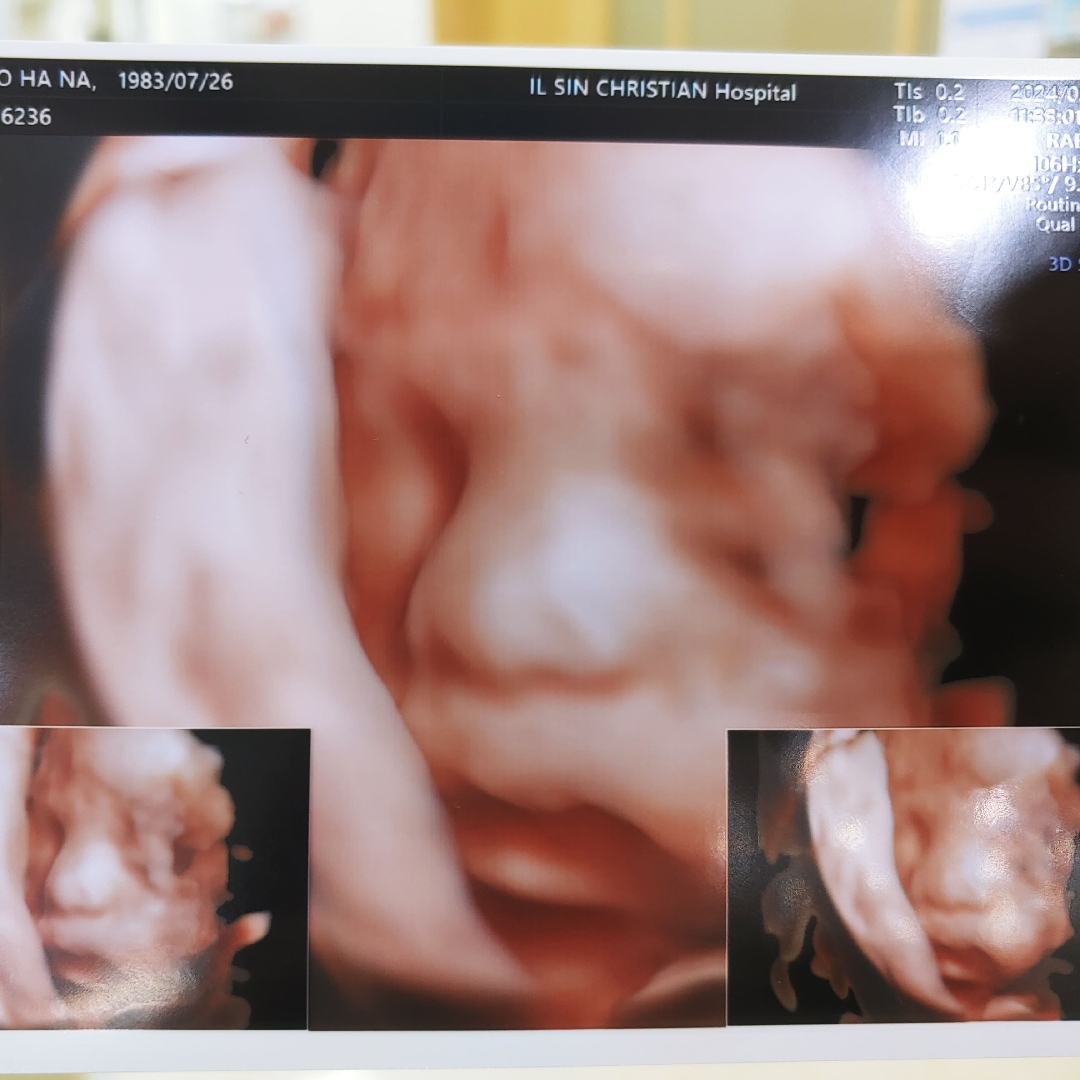

29주차 입체 초음파~^^

다소 흐리긴 하나 아들 얼굴보기 성공했네요~ 24주 차에 찍었던 입초는 뭔가 인상파(?) 같아서 보자마자 몬생겼네~했는데.. 5주 사이 살이 올라 귀여워 진 거 같아요~ 이렇게 도치맘이 되어가는 거겠죠??ㅎ